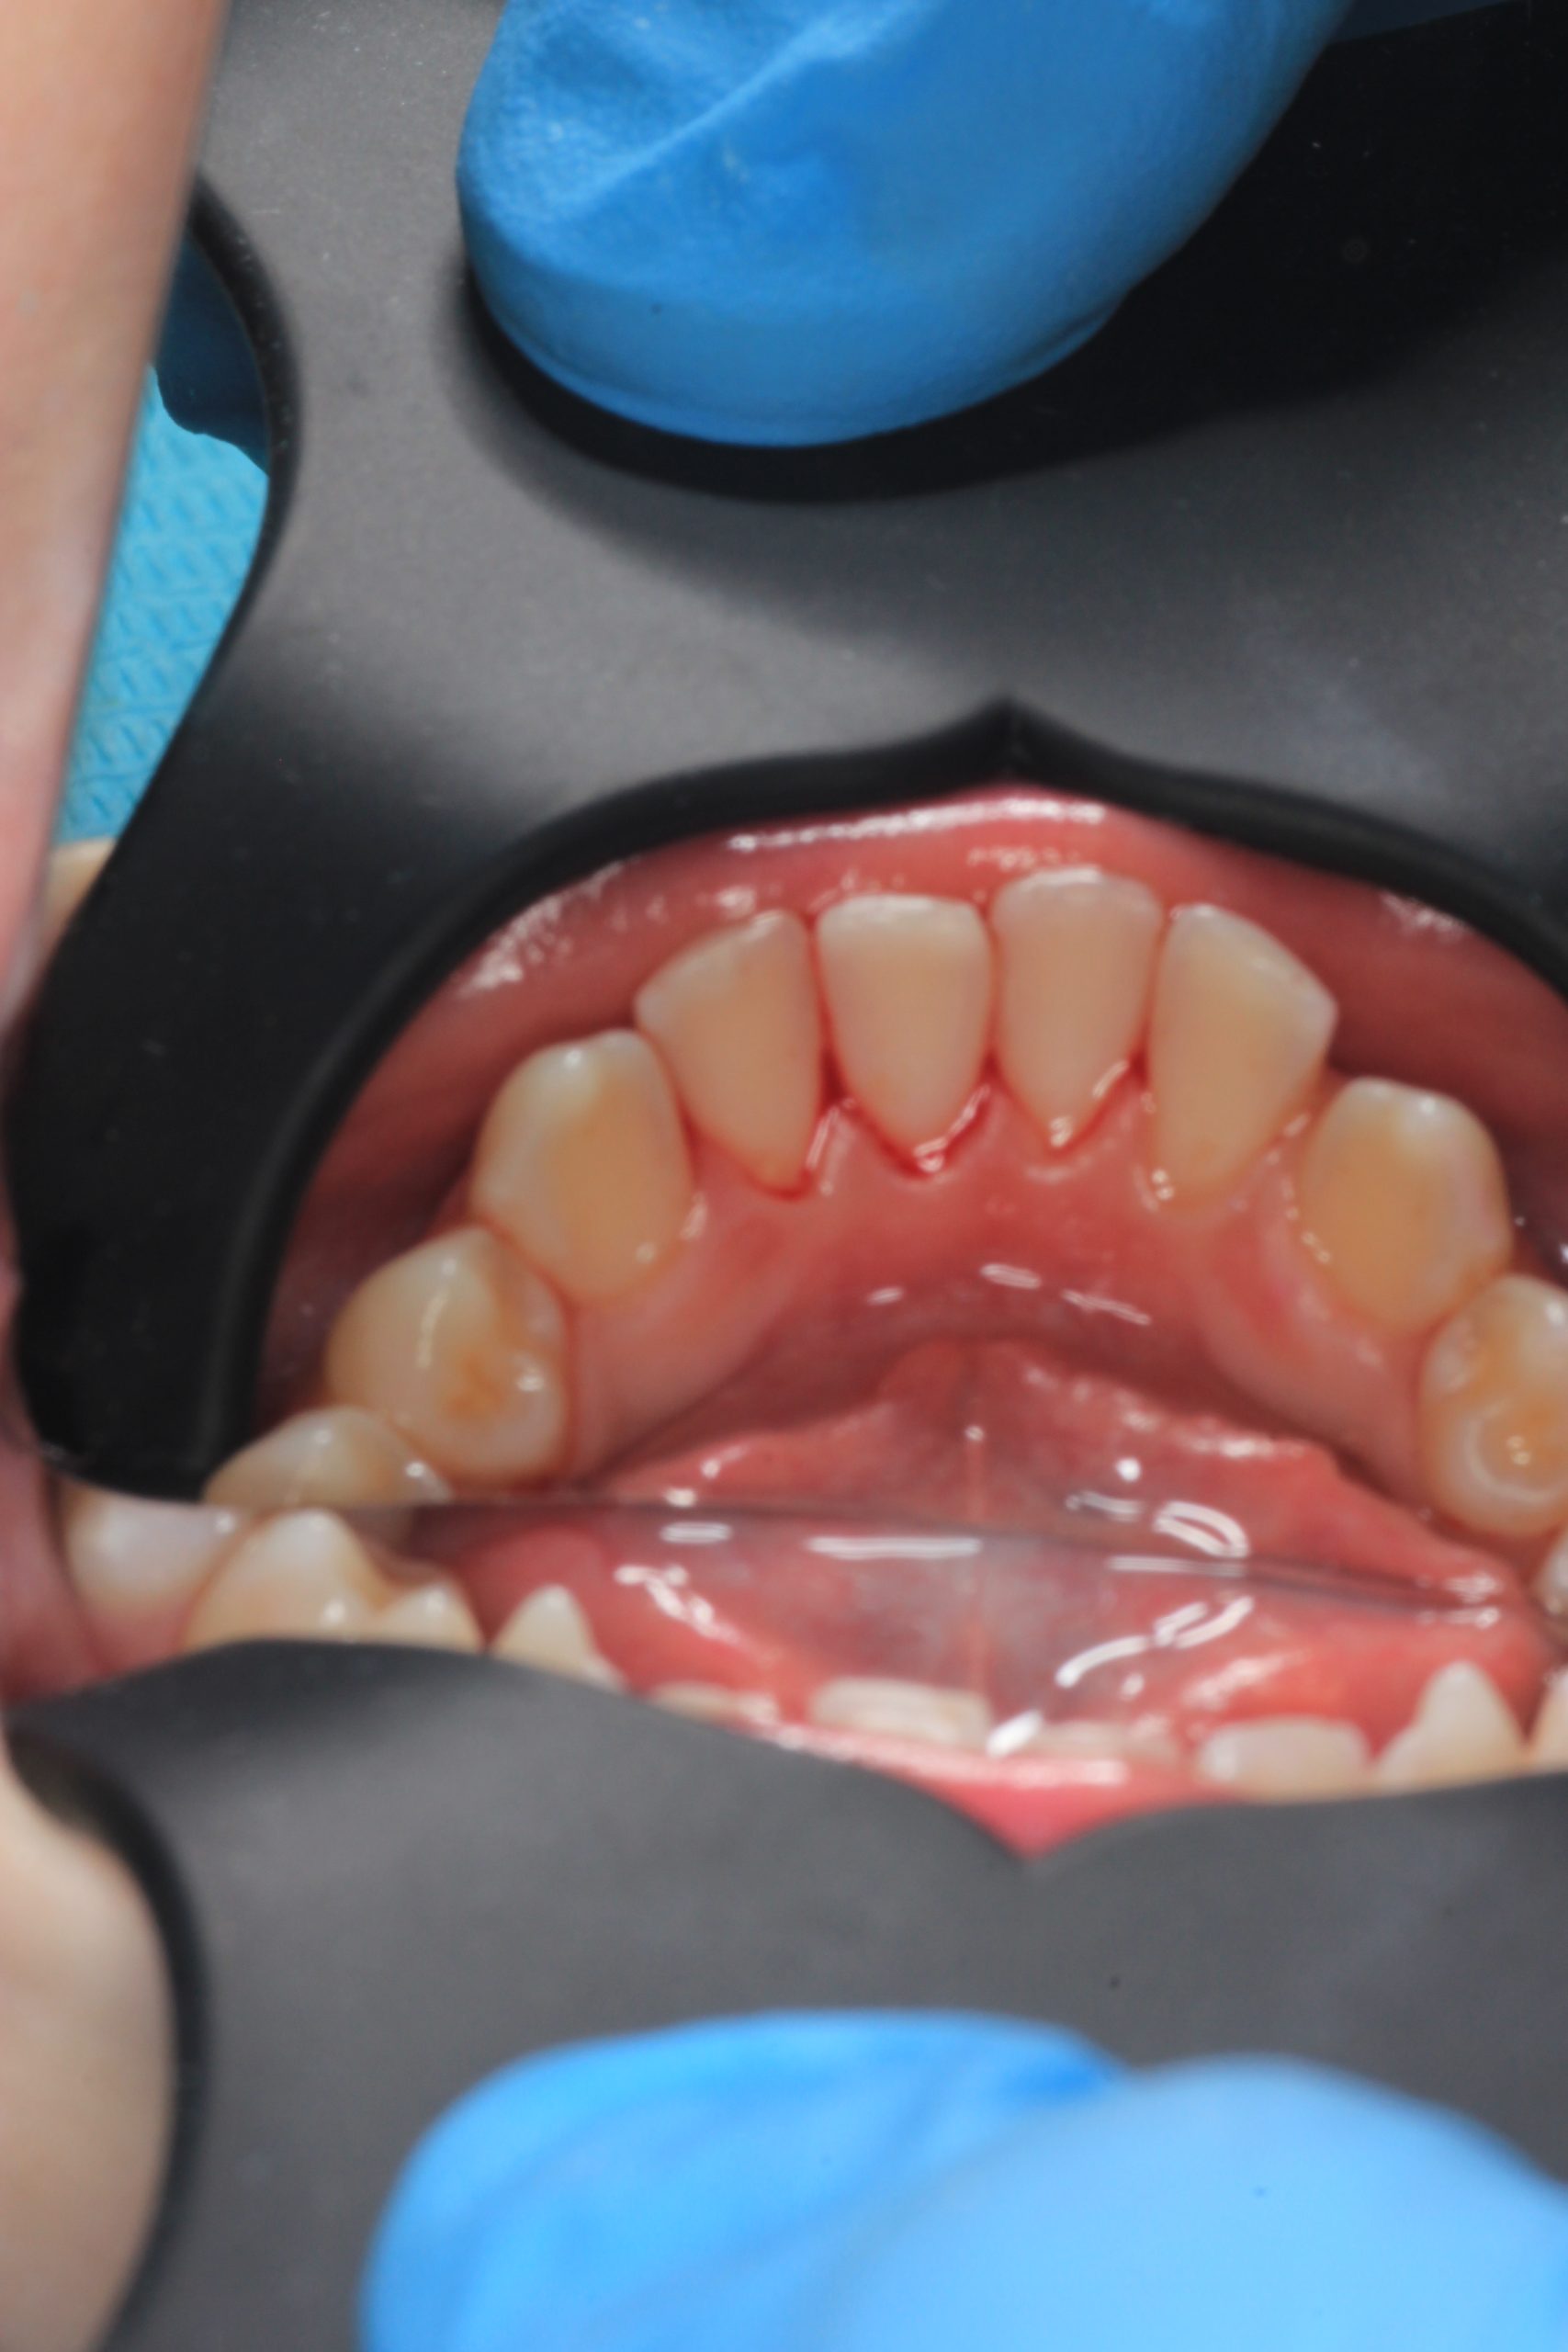

We examine the condition of teeth, gums, and bite. - Plaque Disclosure with Special Indicators

Areas that weren’t cleaned well appear purple. The darker the shade, the older the plaque. This helps both kids and parents understand where brushing needs to improve. - Brushing Training & Home Care Tools Selection

Any tartar is removed gently and painlessly. - Final Check-Up + Fluoride Protection